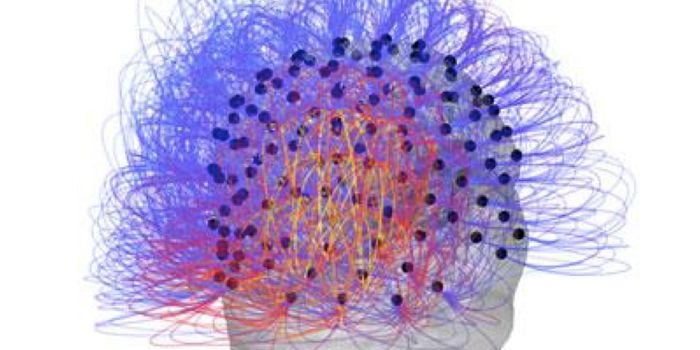

Read the latest articles about newly released neuroscience research and advances in experimental techniques. Topics include research news in neuroscience, neurology, psychology, brain science and cognitive sciences.